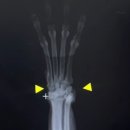

리니혀니예요! :) ​ ​ 오늘은 강아지 발목 삐끗할 때, 발목인대 늘어났을 때 대처방법 및 펫츠오앤피 발목보호대 후기에 대해 자세하게 적어보겠습니다. ​ 강아지 펫츠오앤피 보호대 앞발목 버전 ​ 오른쪽 발목인대 늘어난 강아지 엑스레이 사진 ​ ​ 강아지 발목인대 삐끗 응급처치 발목인대 늘어났을 때 대처방법 ✅ 안정...